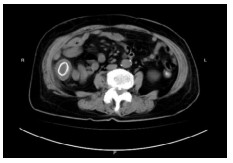

病例3,患者男,33岁。2019年7月6日因“上腹部胀痛10余天”来院急诊,拟“肠梗阻”收治入院。入院查体:腹膨隆,上腹部正中压痛,无反跳痛。CT提示:①横结肠局部肠壁增厚伴管腔狭窄,近段肠管梗阻扩张(图 4);②右肝后段低密度影,建议MR增强。肝脏MR增强:①横结肠局部肠壁明显增厚伴强化,考虑横结肠癌;②肝内多发小斑点,转移瘤可能。肠镜检查示:横结肠肿物,取病理活检后,行肠镜下横结肠支架置入术。肠镜病理提示:横结肠印戒细胞癌。3 d后复查腹部平扫CT示原先扩张的肠腔已明显缩小(图 5)。经多学科讨论后认为目前患者急性肠梗阻症状已明显缓解,建议转肿瘤内科先行转化治疗。患者分别于2019年7月19日、8月7日和8月29日共行三次FOLFIRI方案化疗。2019年9月20日复查腹部增强CT示:横结肠癌支架术后,较前相比,局部肠壁增厚明显减轻;右肝低强化结节灶较前缩小。于2019年9月23日转入普外科,术前再次行多学科讨论后,于10月4日行腹腔镜下横结肠癌切除手术(图 6),手术过程顺利。术后病理报告:横结肠印戒细胞癌,T3N1M1。患者术后接受定期规律辅助化疗,目前恢复良好。

| 图 4 腹部增强CT示横结肠、升结肠及近段小肠肠管梗阻扩张明显 |